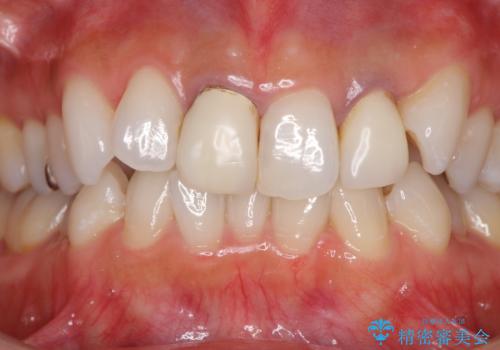

- 20年ほど前に被せた前歯のメタルボンドクラウンの色合いを気にして来院された患者様です。

2歯をオールセラミッククラウン(ジルコニアクラウン)にて補綴することとしました。

裏打ちが金属の場合、どうしても金属色を遮蔽しないとならないため、透明感のない色合いとなってしまいます。